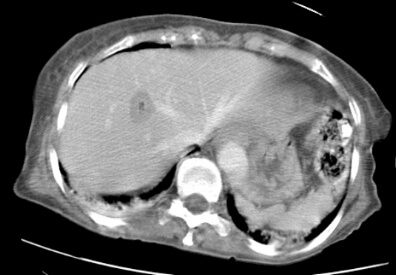

This is a CT image obtained after microwave ablation demonstrating the tumor and surrounding area affected by the procedure.